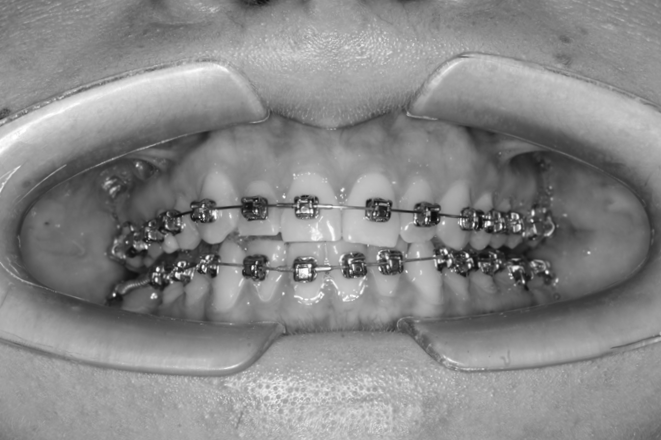

The results of the conducted studies allowed us to move on to orthodontic treatment, which consisted of the sequential application of the bracket system first to the teeth of the upper jaw; wearing of the occlusal splint continued at this stage (Fig. 6).

Fig. 6. Braces on the teeth of the upper jaw

After three months, the bracket system was fixed to the lower row of teeth (Fig. 7) and fixation of photocomposite overlays, which in this clinical case were located in the area of teeth 1.6, 2.6, wearing of the splint was completed at this stage (Fig. 8).

Fig. 7. The stage of applying the brace system to the teeth of the lower jaw